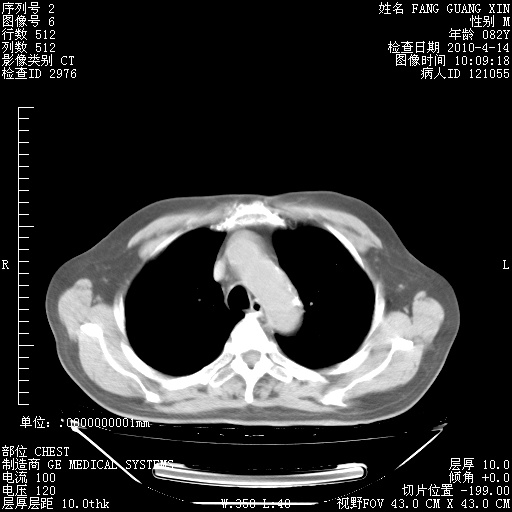

4月14日肺部CT

肺部CT平扫未见异常。